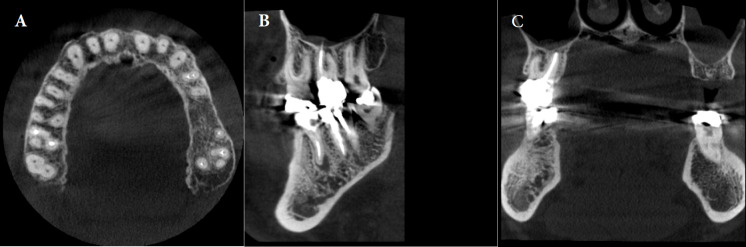

Results: Of the 2053 teeth examined, 14.9% had at least one untreated canal. Untreated canals in teeth increase the chance of having a periapical lesion, raising the prevalence by 11 times. Of these, 91.8% had both untreated canals and periapical lesions. This was more than teeth without untreated canals (35.8%). Most untreated canals were in maxillary molars (65.3%), and mandibular molars (12.54%). There was a statistically significant relationship (P<0.001) between the number of roots, canals, expansion, destruction, and jaw type with the prevalence of untreated canals. The maxillary first molar (68.66%) and second mesiobuccal (MB2) canal (63.27%) had the highest percentages of untreated canals.

Conclusions: The MB2 had the highest prevalence of untreated canals. The presence of untreated canals significantly increased the risk of expansion and/or destruction. Therefore, identifying these conditions can also be useful in diagnosing untreated canals. Dentists should assess the anatomy of the tooth and the structure of the root canal to minimize the possibility of an untreated canal. CBCT can assist in this process.